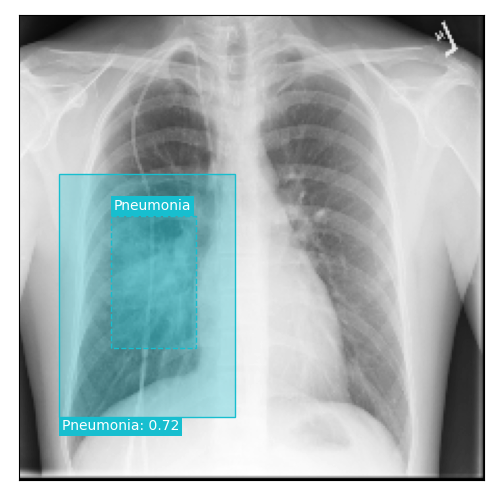

Qualitative Results

As shown in Fig. 4 Loc-ADPD detects cardiomegaly almost perfectly, as it is always exactly localized at one anatomical region. Other pathologies are detected but often with too large or too small boxes as they only cover parts of anatomical regions or stretch over several of them, which cannot be completely corrected using WBF. Detection also works well for predicting several overlapping pathologies. For qualitative comparisons between Loc-ADPD and MIL-ADPD, we refer to Appendix 0.B.